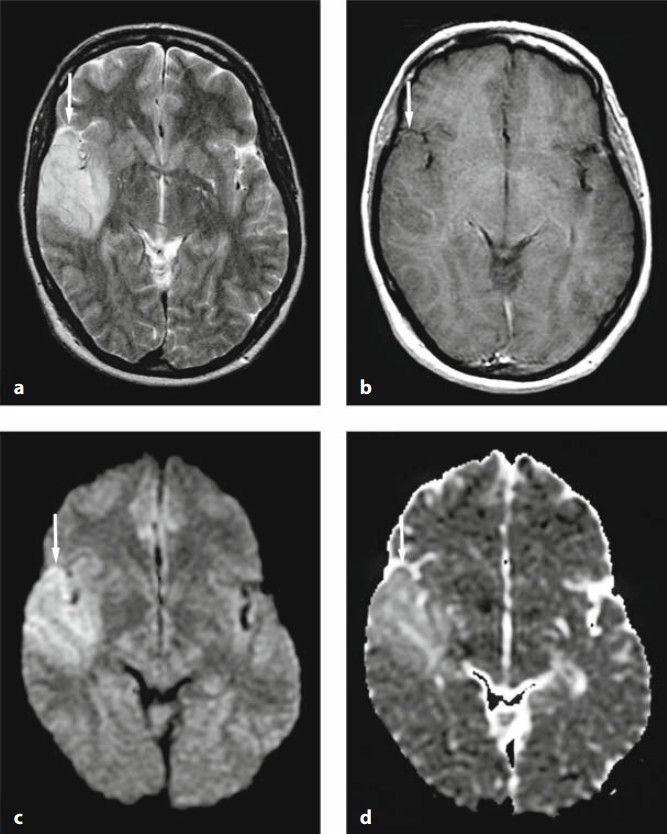

57a7d86023ddc89dc17cb638e3ee9951.jpg

图 3 花边征(飘带征),散发型 CJD 患者,A、B 为 DWI,C 为 ADC 图,D 为 FLAIR。可见患者双侧皮层不对称的 DWI 高信号(箭头),基底节区 DWI 高信号(三角箭头),病灶 ADC 图上为低信号,FLAIR 上高信号